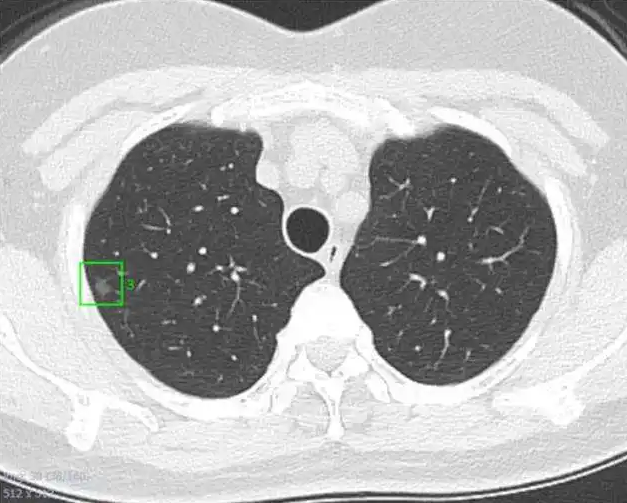

在影像学上把肺部阴影按照直径大小分为肺结节和肺肿块。

肺结节为直径≤3 cm的局灶性、类圆形、密度增高的实性或亚实性肺部阴影,可为孤立性或多发性。

局部病灶直径>3 cm者称为肺肿块,肺癌的可能性相对较大。

形成肺结节的原因有很多种,常见的有:恶性肿瘤(原发性肺癌、肺转移瘤、类癌)、感染性肉芽肿、良性肿瘤(如错构瘤)、血管性病变和炎性病变等。

所以,发现肺结节不等于就是患上了肺癌。